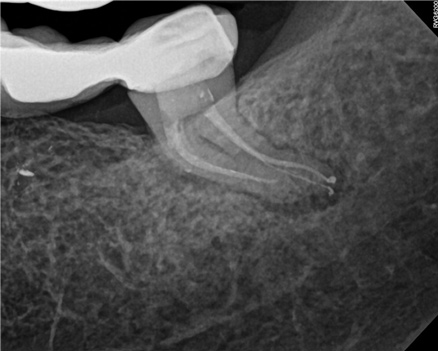

In the first case study, a young female patient was told she had a tooth (tooth No. 2, Figure 3) that should be extracted due to extensive bone loss. Using CBCT, the clinician was able to identify a large lateral canal within the palatal root. Despite the bone loss, the patient was eager to save her tooth. He offered to treat the tooth with the broad-spectrum acoustic technology. As shown in Figure 4, the preparation space was much smaller, which he was able to obturate efficiently. In addition, the small pinpoint of sealer in the middle of the palatal root indicated that the palatal lateral canal had been addressed (Figure 5). In the clinician's opinion, this area was likely the primary source of much of the bone loss.

Figure 6 through Figure 8 demonstrate that, 5 months after the procedure, complete healing had occurred, notably on the distal, where the probing had resolved to 2 mm. The patient then had a crown placed by her general dentist. Given her positive experience with the technology, she was eager to return as needed for continued follow-up.

Fig 3. Case 1: CBCT showed a large lateral canal within the palatal root (Fig 3). There was a small preparation space, which was efficiently obturated (Fig 4). A small pinpoint of sealer in the middle of the palatal root indicated that the palatal lateral canal had been addressed (Fig 5). After 5 months, CBCT demonstrated complete healing (Fig 6), notably on the distal, where probing had resolved to 2 mm. Radiographic images were taken immediately postoperatively (Fig 7) and 5 months postoperatively (Fig 8).

Fig 4. Case 1: CBCT showed a large lateral canal within the palatal root (Fig 3). There was a small preparation space, which was efficiently obturated (Fig 4). A small pinpoint of sealer in the middle of the palatal root indicated that the palatal lateral canal had been addressed (Fig 5). After 5 months, CBCT demonstrated complete healing (Fig 6), notably on the distal, where probing had resolved to 2 mm. Radiographic images were taken immediately postoperatively (Fig 7) and 5 months postoperatively (Fig 8).

Fig 5. Case 1: CBCT showed a large lateral canal within the palatal root (Fig 3). There was a small preparation space, which was efficiently obturated (Fig 4). A small pinpoint of sealer in the middle of the palatal root indicated that the palatal lateral canal had been addressed (Fig 5). After 5 months, CBCT demonstrated complete healing (Fig 6), notably on the distal, where probing had resolved to 2 mm. Radiographic images were taken immediately postoperatively (Fig 7) and 5 months postoperatively (Fig 8).

Fig 6. Case 1: CBCT showed a large lateral canal within the palatal root (Fig 3). There was a small preparation space, which was efficiently obturated (Fig 4). A small pinpoint of sealer in the middle of the palatal root indicated that the palatal lateral canal had been addressed (Fig 5). After 5 months, CBCT demonstrated complete healing (Fig 6), notably on the distal, where probing had resolved to 2 mm. Radiographic images were taken immediately postoperatively (Fig 7) and 5 months postoperatively (Fig 8).

Fig 7. Case 1: CBCT showed a large lateral canal within the palatal root (Fig 3). There was a small preparation space, which was efficiently obturated (Fig 4). A small pinpoint of sealer in the middle of the palatal root indicated that the palatal lateral canal had been addressed (Fig 5). After 5 months, CBCT demonstrated complete healing (Fig 6), notably on the distal, where probing had resolved to 2 mm. Radiographic images were taken immediately postoperatively (Fig 7) and 5 months postoperatively (Fig 8).

Fig 8. Case 1: CBCT showed a large lateral canal within the palatal root (Fig 3). There was a small preparation space, which was efficiently obturated (Fig 4). A small pinpoint of sealer in the middle of the palatal root indicated that the palatal lateral canal had been addressed (Fig 5). After 5 months, CBCT demonstrated complete healing (Fig 6), notably on the distal, where probing had resolved to 2 mm. Radiographic images were taken immediately postoperatively (Fig 7) and 5 months postoperatively (Fig 8).